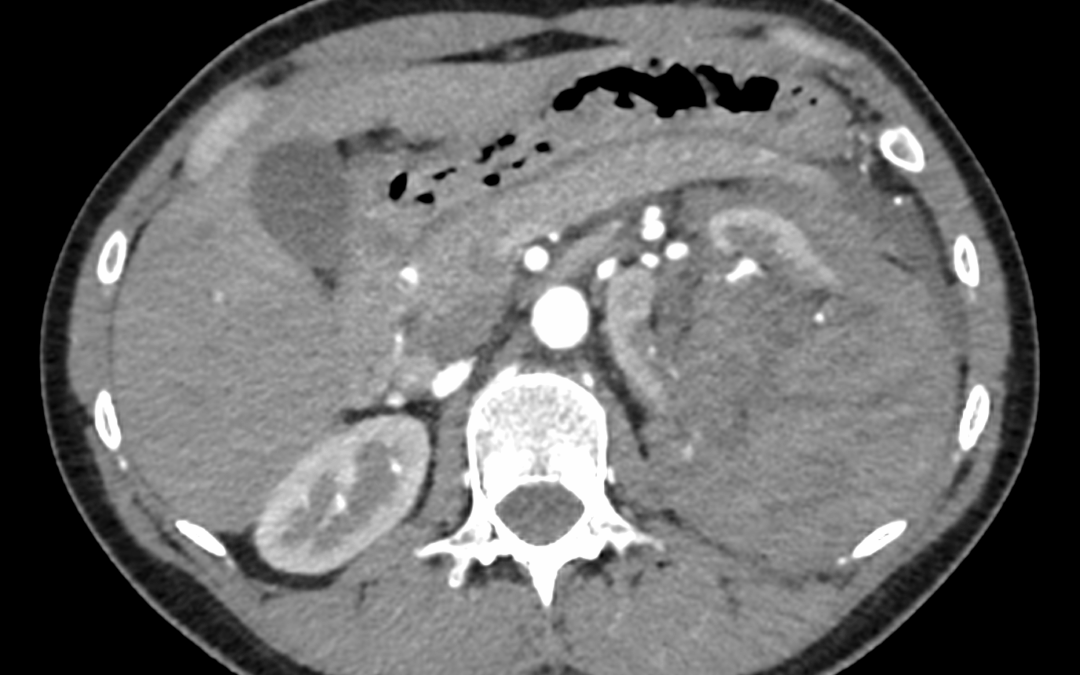

Mujer de 28 años, natural de Afganistán, llegada a España 9 días antes de las pruebas , derivada a nuestro hospital para estudio de masa pélvica con afectación ósea.Antecedentes personales:– Sin reacciones adversas medicamentosas conocidas– No hábitos tóxicos–...